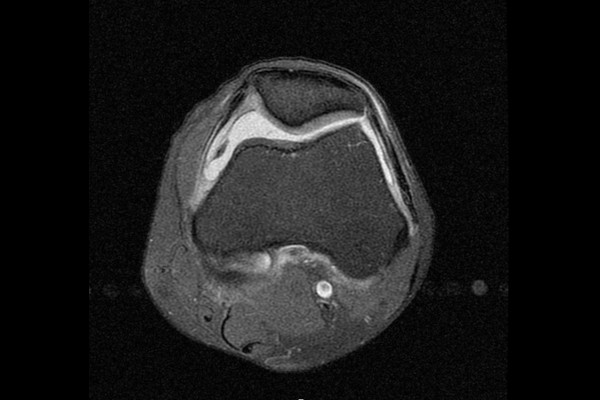

또한 무릎 관절내에 물이 차있는 것이 확인되었고 무릎 추벽증후군(Plica syndrome knee)으로 진단하였습니다.